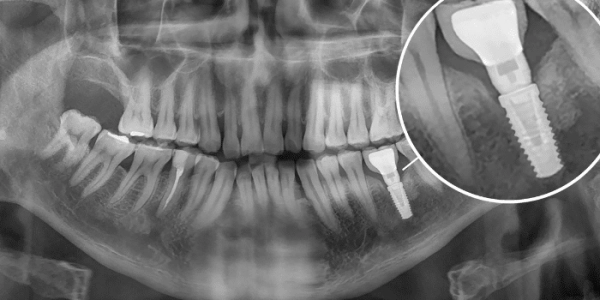

The failure rate of dental implants is significantly higher in smokers. Before proceeding with dental implant surgery, your dentist or oral surgeon will evaluate your overall health and discuss any potential risks with you.As with any dental procedure, it is advisable to visit Batal Dental Center in Saudi Arabia, where there is a highly trained and qualified medical team specialized in this field.Read also: Who Is a Candidate for Dental Implants in Detail?

Although dental implant failure is uncommon, it can occur—especially in smokers who do not follow post‑operative care instructions. If an implant fails, the person may notice the following symptoms:If any of the above symptoms appear, you should visit Batal Dental Center in Saudi Arabia. The dental team will follow the appropriate treatment protocols to preserve your oral health and manage dental implants for smokers as safely as possible.Read also: Treating Toothache with Herbal Remedies